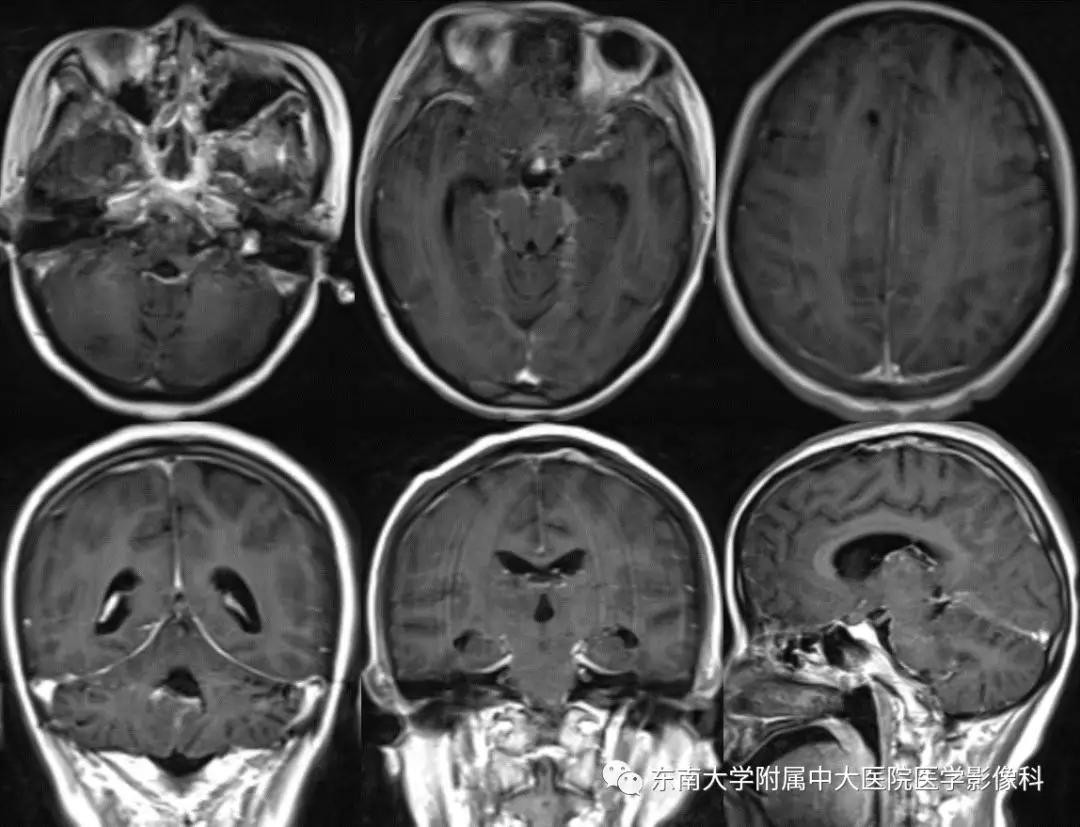

病例2

病史

女,27岁,因“阵发性头痛1月,发热4天,意识障碍1天”入院。

外院行胸部CT平扫示:两肺弥漫型渗出性病变;父亲有“结核”病史。

MR

增强

病例结果:病例1脑膜瘤;病例2结核性脑膜炎并急性脑梗塞。